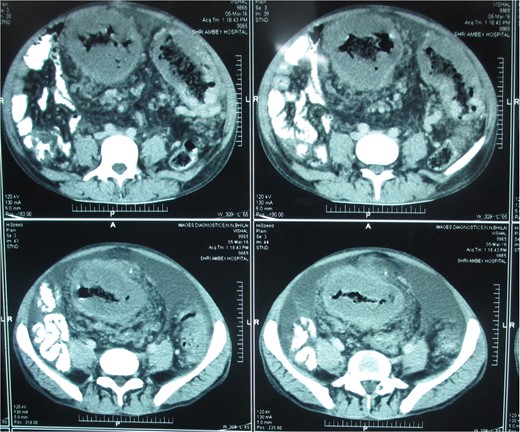

Postcontrast axial images of the abdomen showing irregular wall thickening involving the distal desceding colon, sigmoid colon and rectum without significant luminal narrowing. Heterogenous enhancement of the thickened bowel wall with mild pericolic fat stranding.